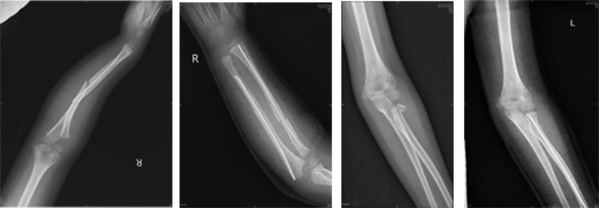

徐醫(yī)附院小兒骨科依托省級臨床重點?乒强破脚_,擁有雄厚的醫(yī)療、科研實力,配備了脊柱手術(shù)顯微鏡、術(shù)中導航、脊柱微創(chuàng)內(nèi)鏡、關(guān)節(jié)鏡設備、術(shù)中神經(jīng)電生理監(jiān)測、超聲骨刀等先進設備,極大地保證了患兒高難手術(shù)的精準性和安全性。自2022年2月17日成立以來,徐醫(yī)附院小兒骨科秉承“微創(chuàng)化、精準化”的治療原則,為淮海經(jīng)濟區(qū)兒童骨科患者提供優(yōu)質(zhì)的醫(yī)療服務,贏得了廣泛贊譽。當前,徐醫(yī)附院小兒骨科每月完成手術(shù)近40余臺。小兒肱骨髁上骨折、前臂骨折、股骨干骨折等常見骨折基本上都是經(jīng)皮微創(chuàng)完成,獲得患兒家長的好評和信任。